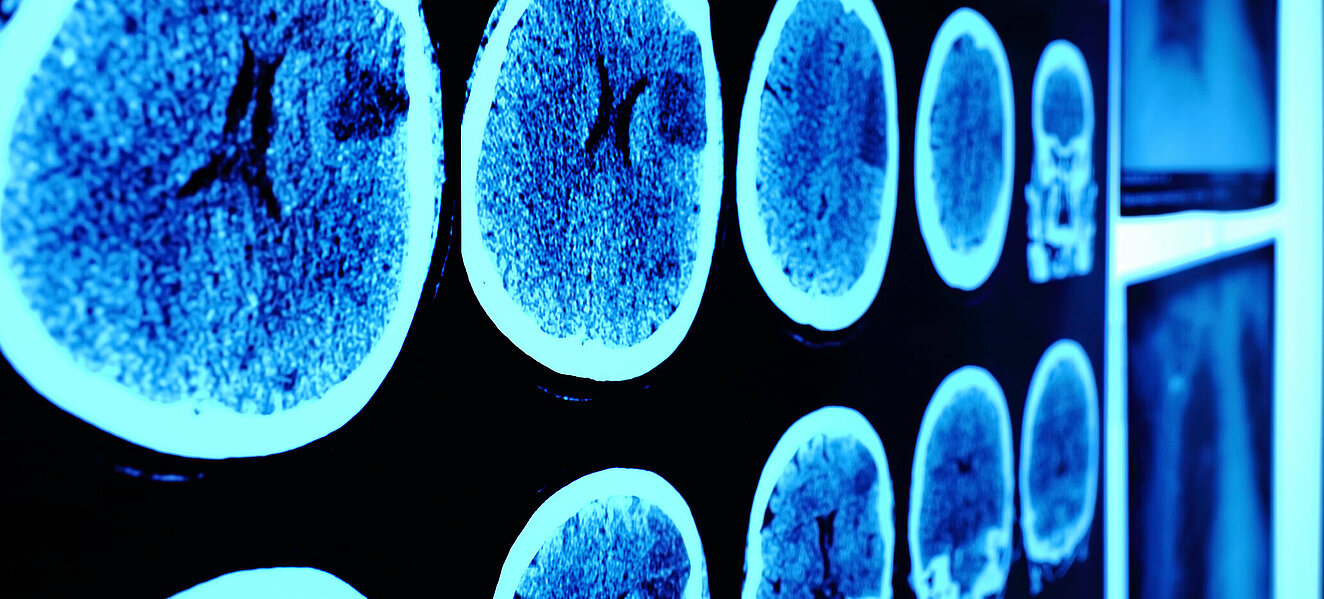

Hirntumor

STERBEN MIT ANSAGE

Dmitrij litt unter permanenter Übelkeit, Rückenschmerzen und wurde zwischendurch auch schon einmal ohnmächtig. Im Dezember 2011 erhielt der damals 20jährige dann die Diagnose: bösartige Zellwucherungen im Gehirn. Erleichtert darüber, die Ursache für die quälenden Beschwerden zu kennen, trat er die Operation an, es folgten zahlreiche Bestrahlungen und Chemotherapien. „Wäre nicht schlecht, wenn es an dieser Stelle enden könnte“, schreibt er in seinem Blog. Doch nach zwei krebsfreien Jahren kommt es zum Rückfall, Ende 2015 wurde zudem bei einer Untersuchung des Nervenwassers festgestellt, dass bereits Hirnmetastasen vorliegen.

Klassifikation Dmitrij ist an einem sogenannten Medulloblastom, einem bösartigen embryonalen Tumor des Kleinhirns, erkrankt. Meist tritt er im Kleinkindes- oder Kindesalter auf und gilt als häufigster bösartiger Gehirntumor in dieser Altersstufe. Bei Erwachsenen ist das Medulloblastom relativ selten und macht nur etwa ein Prozent aller Hirntumoren aus. Laut der Gliederung der Weltgesundheitsorganisation zählt die Wucherung zu den Tumoren des zentralen Nervensystems (Grad IV).